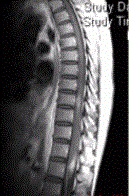

- 多项选择题3.关于MRI的描述正确的是(提示患者行脊柱MRI平扫及增强检查,显示如下图)

A、颈髓增粗,其内可见片状高信号影

B、胸髓可见多发片状高信号影

C、脊髓未见异常

D、MRI增强检查可见片状强化

E、脊髓空洞

F、脊髓肿胀

- 多项选择题4.根据脊髓和头部MRI表现,病变应诊断为

A、多发脑缺血

B、多发性硬化

C、脑白质稀疏

D、脑萎缩

E、脑炎

F、脑白质病变